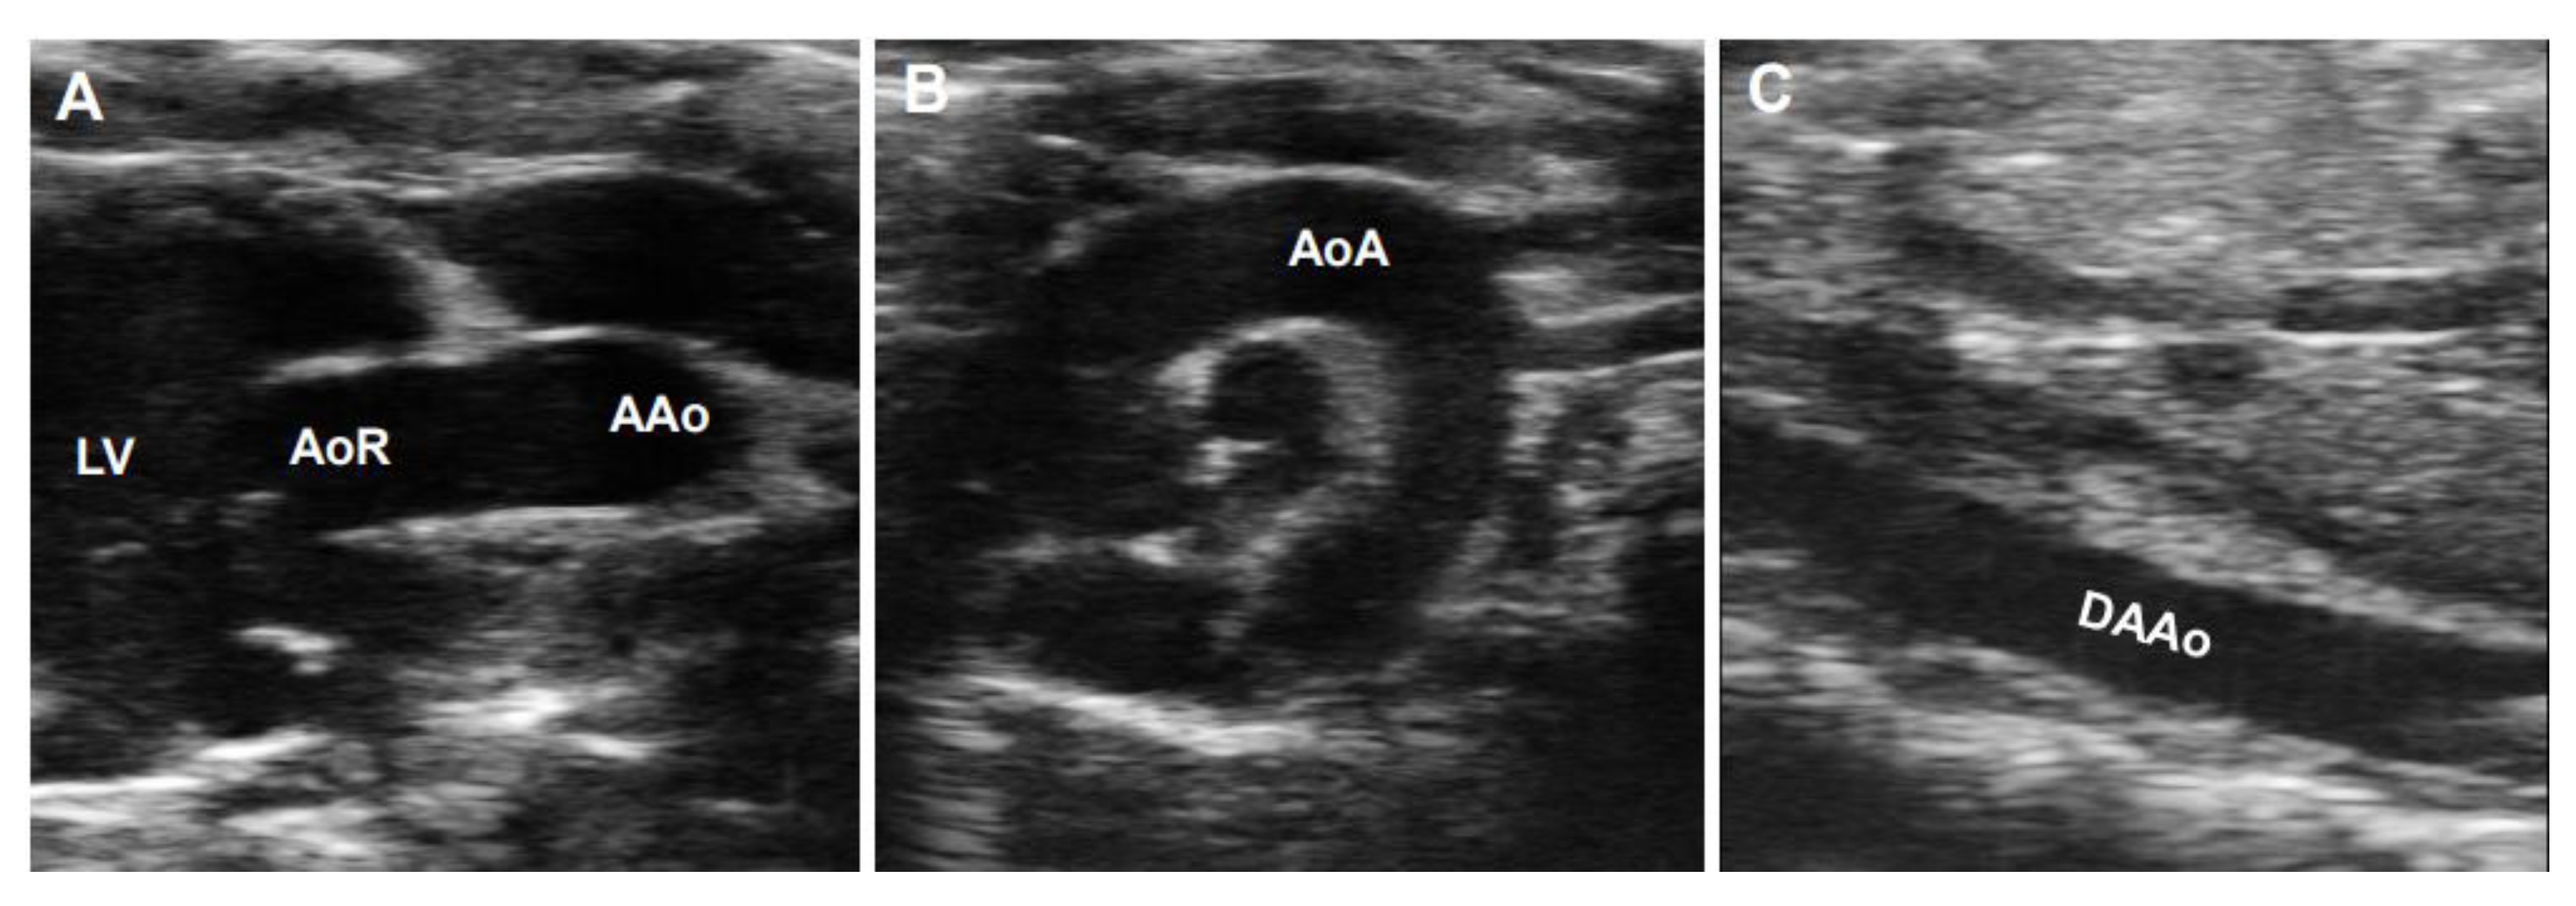

B-mode ultrasonography, also known as two-dimensional (2D) ultrasonography, is one of the most basic ultrasound models that produces a real-time black/white image of the targeted site, where the aortic wall is shown as echo-reflecting and the lumen as echo-free. As shown in Figure 3, the ultrasonographic view of the aorta is either circular in the perpendicular sections or tube-shaped in the parallel sections in humans. For example, the AoR and the AAo could be visualized in the parasternal long-axis view (Figure 3A), the modified right parasternal long-axis view, modified apical five-chamber (Figure 3B), and three-chamber views (Figure 3C). Additionally, the suprasternal view is a crucial view to visualize the AoA and the three supra-aortic trunks (innominate, left carotid, and left subclavian arteries), and a variable tract of the AAo and the DTAo (Figure 3D). In some cases, the entire arch could not be visualized in a single image plane because of the aorta’s extreme tortuosity. The DTAo can also be displayed in the posterior field through the cardiac acoustic window (Figure 3E). Moreover, parts of the DTAo may be invisible due to the tracheal air. The subcostal views may be helpful and allow the DAAo to be visualized (Figure 3F). Although B-mode has been widely used in humans, its application in mouse aorta remains relatively challenging, primarily because of the difficulty in obtaining exceptional spatial and temporal resolution in a small, rapidly varying vessel. Since apical views of the heart are prone to change in rodents, particularly in mice, it is difficult to obtain stable images of the aorta in this view. Reciprocally, the parasternal (Figure 4A), suprasternal (Figure 4B), subcostal, and transabdominal views (Figure 4C) are the most critical views for murine aorta, which enable an adequate assessment of the AoR, the AAo, and most of the segments of the DTAo and DAAo in mouse models.

Figure 4. B-mode imaged segments of a mouse aorta. (A): The parasternal long-axis view of the aortic root (AoR) and the ascending aorta (AAo). (B): The suprasternal view of the aortic arch (AoA). (C): The subcostal view of the descending abdominal aorta (DAAo). LV: left ventricle.